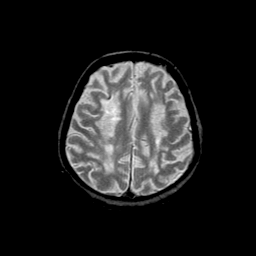

Basal Ganglia Calcification: T2-weighted MR -- Slice #13

[Home][Help][Clinical] Slice 13